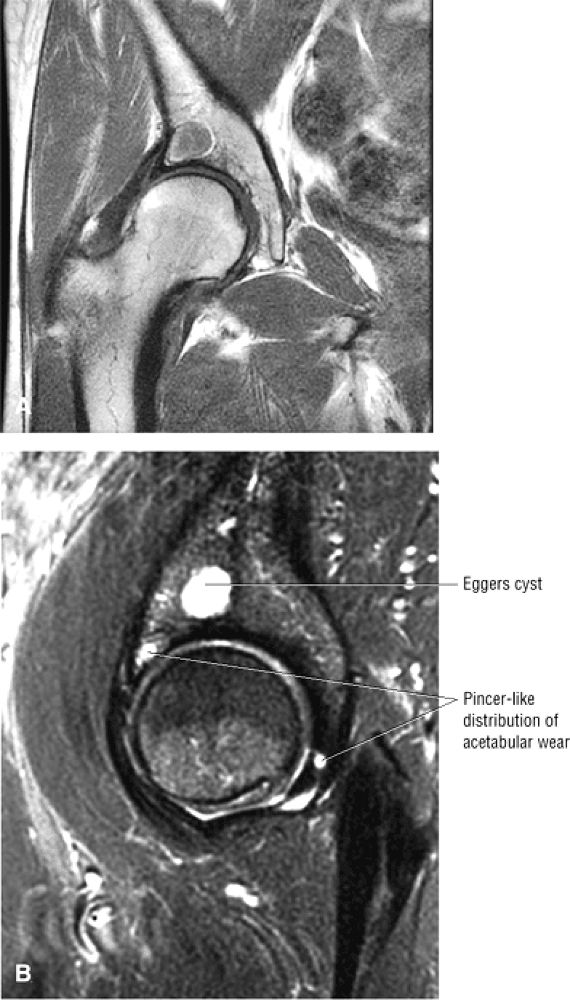

FIGURE 3.30 ● Normal sagittal anatomy of the hip. (A and B) On medial sagittal images, the course of the obturator internus, piriformis, and the adductor muscles can be followed and analyzed for strain injury or tears. (C and D) Tendinosis and tears of the common hamstring tendon origin on the ischial tuberosity are optimally viewed at this location and are extremely common in middle aged and elderly patients. (E and F) Although thinning and fraying of the articular cartilage can occur anywhere in the joint, chondral degeneration is most commonly seen first in the anterior superior quadrant, often accompanied by anterior labral tears, subchondral edema, and cystic change in the anterior acetabulum. When any one of these findings is present, a careful search for the others should be performed. (G and H) Linear tears of the anterior labrum can be mimicked by fluid filling a normal recess between the anterior labrum and the anterior joint capsule. Imaging in the axial and coronal planes is used to distinguish between a true tear and the normal recess, since a tear is visualized and confirmed in the axial and coronal planes, whereas a recess is only seen prominently in the sagittal plane. (K and L) The gluteus medius and minimus tendons have been referred to as the “rotator cuff” of the hip. The gluteus medius tendon inserts posteriorly on the greater trochanter, and the gluteus minimus tendon inserts anterolaterally on the greater trochanter. (I and J) Loose bodies commonly lodge in the joint recesses anterior and posterior to the femoral neck (deep to the iliofemoral and ischiofemoral ligaments). They are commonly seen (particularly in the sagittal plane) in patients with chondral degeneration. (M and N) Acute tears of the gluteus medius and minimus often mimic symptoms of a proximal femoral fracture. Chronic partial tears and tendinosis are frequently associated with trochanteric bursitis, and are common in middle-aged and elderly patients.